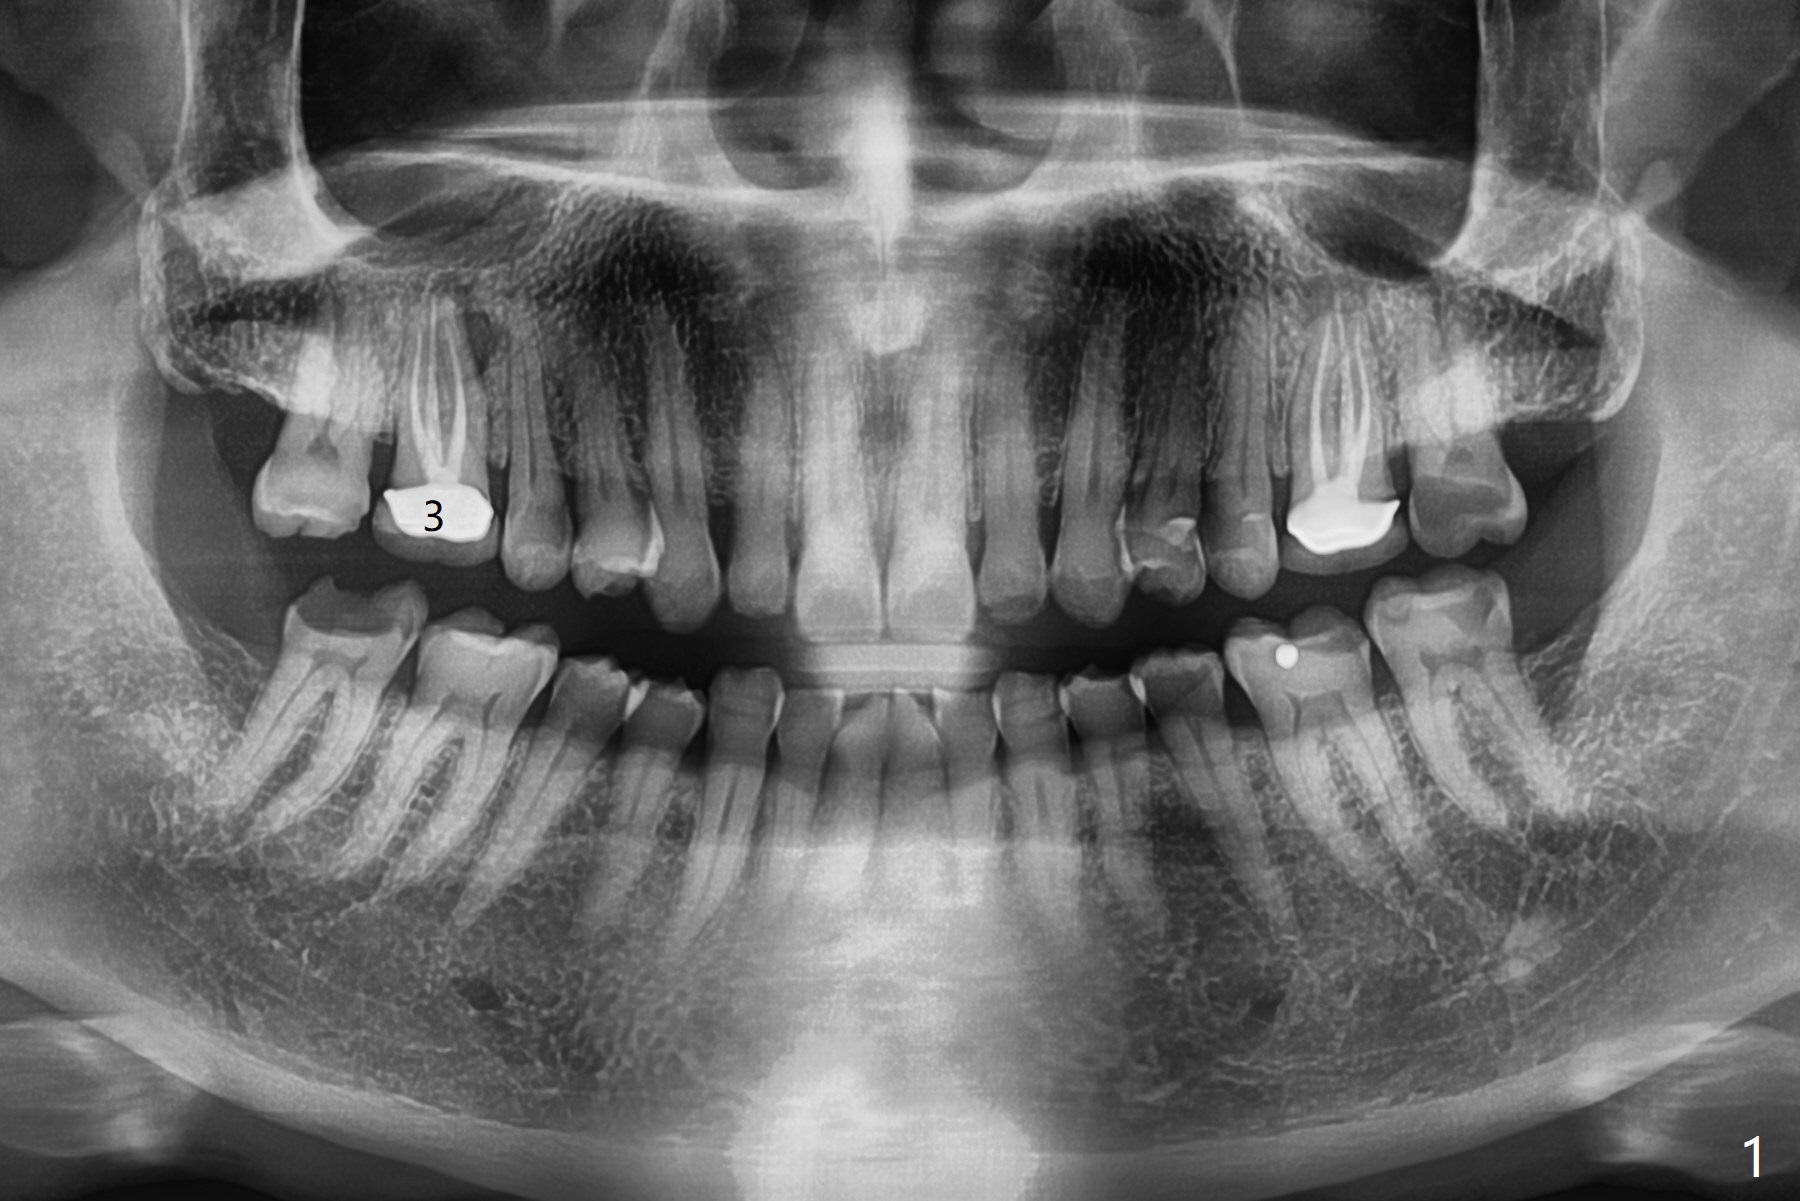

A 56-year-old man with signs of bruxism (multiple occlusal wear and tear, Fig.1) returns from an endodontist office because of failed RCT retreatment at #3 (Fig.2 (* palatal swelling; > fistula)). After difficult extraction, the socket is large without much septal bone (Fig.3 *). Because of lack of the apical native bone, immediate implant is not placed. If it has to be done, a large and long one is required. Instead socket preservation is finished (Fig.4 *). The socket is 20 mm deep, while the shank of surgical curettes is 20 mm. It appears that the most apical granulation tissue is hard to be removed. When 7-day oral Clindamycin is finished, the patient returns with chief complaint of recurrent pain and fistulae. In fact the palatal fistulae are flat without erythema. He returns asymptomatic 2 weeks postop; the fistulae are disappearing (Fig.5 ^) and the socket is healing (Fig.6).